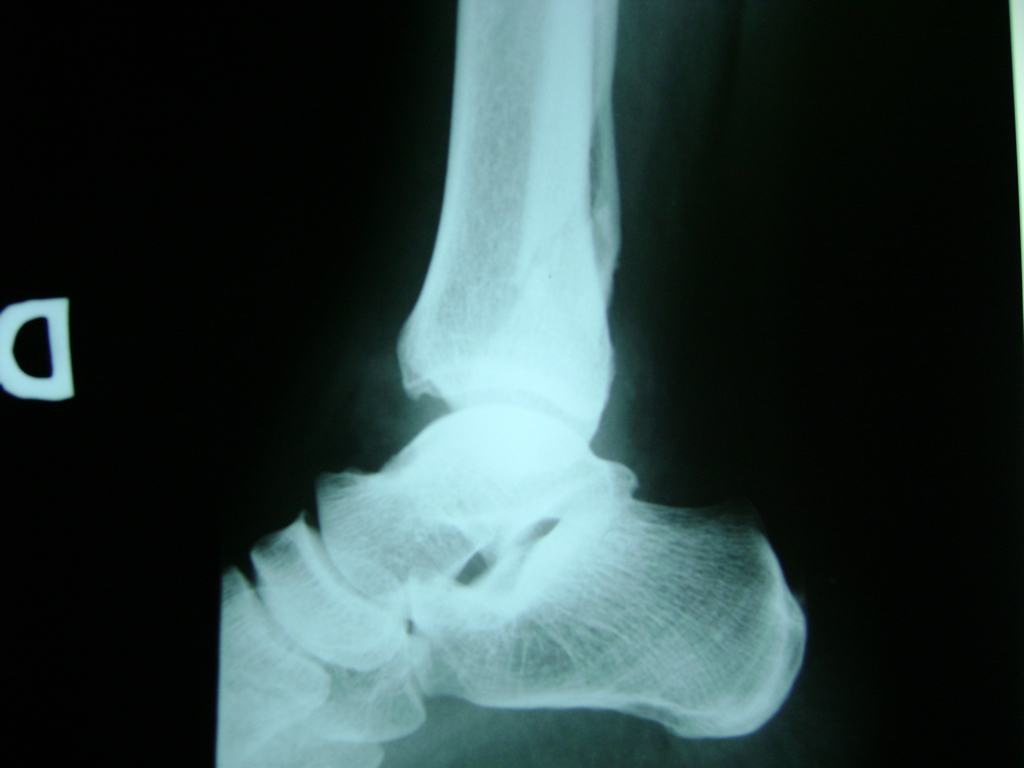

Una fractura de tobillo es la rotura de uno o más de los huesos del tobillo. Estas fracturas pueden ser:

- Parciales (el hueso está sólo parcialmente fisurado, no del todo).

- Completas (el hueso está perforado y está en 2 partes).

- Producirse en uno o ambos lados del tobillo.